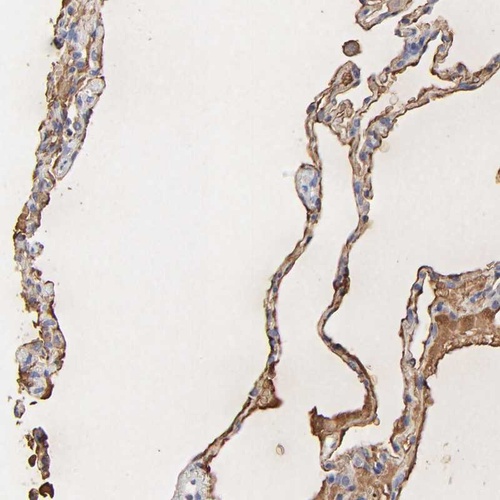

Immunohistochemical staining of human lung shows cytoplasmic and membranous positivity in alveolar cells.